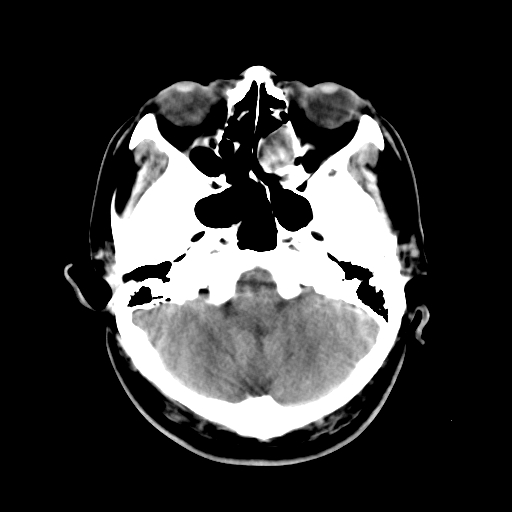

标题: CT15194:男,53岁,头痛、恶心三天。 [打印本页]

男,53岁,头痛、恶心三天。

筛窦粘液囊肿。

筛窦囊肿

楼主是否应该上几幅骨窗观察啊!

考虑筛窦内粘液囊肿可能性大。